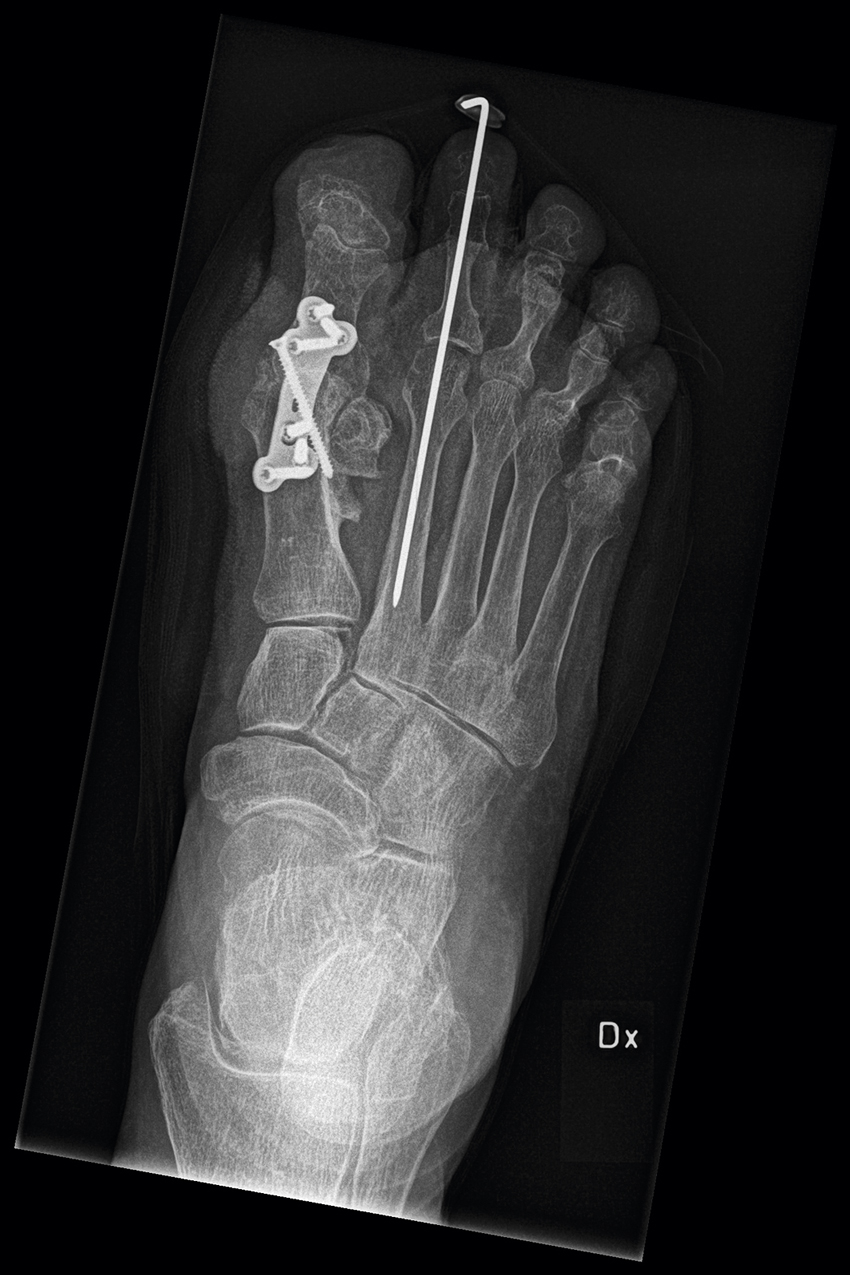

Slätröntgen med belastning hos patient med bilateral hallux valgus. Notera mer uttalad felställning på höger sida.

Artrodes (steloperation) i proximal interfalangeal (PIP)-led I i andra tån på grund av hammartå.